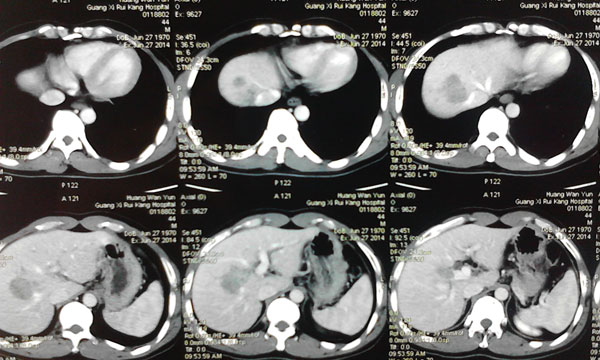

患者确诊为原发性肝癌,肿瘤位于肝脏的ⅦⅧ段,侵犯肝右静脉,与肝中静脉关系密切,必须行右半肝全切除,残留肝体积需达到标准肝体积的40%左右才能保证术后肝功能正常,而患者的残留肝脏体积仅占标准肝体积的30%,传统上认为达不到手术切除的要求。韦杨年主任决定采用世界肝脏外科革命性的二步肝切除技术。

肿瘤的位置